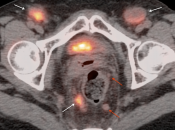

Metastases:

The most common sites of metastatic disease include the lymph nodes (regional & distant), liver, lung, peritoneal cavity, bones, brain and adrenal glands.

- Nodes under 8.0 mm may be non-avid only because they are beneath the resolution of PET (metastatic nodal assessment is discussed in detail, here).

- If < 8.0 mm, even mild uptake in a regional node is “highly suspicious”.

- If < 8.0 mm, even non-avid regional nodes are worrisome, and are considered “indeterminate”.